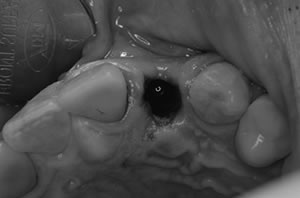

抜歯は周りの骨を損傷しないように、普段の抜歯より細心の注意を払います。

普通は歯肉を開いて、骨を明示して手術をおこなうのですが、この方法だと、歯間乳頭(歯肉の間の三角形の歯肉)とよばれる部位がなくなってしまい、被せものが審美的でないので、上の写真のように‘フラップレス’といって歯肉を開かない方法が推奨されています。

インプラントにヒーリングキャップを装着します。

キャップの上に仮歯がすぐはいります。